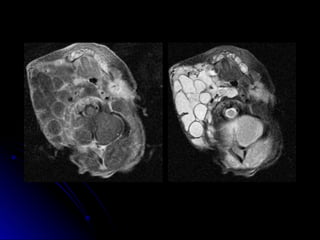

Congenital Cystic Adenomatoid

Malformation (CCAM)

 May be confused with CDH

May be confused with CDH

 Abnormal lung tissue that forms fluid filled

Abnormal lung tissue that forms fluid filled

cysts. May be large cysts, or many small

cysts and solid areas

 Space occupying lesion

Space occupying lesion

 May cause shifting of mediastium

May cause shifting of mediastium

 May spontaneously regress in fetus

May spontaneously regress in fetus

 May require surgical removal

May require surgical removal